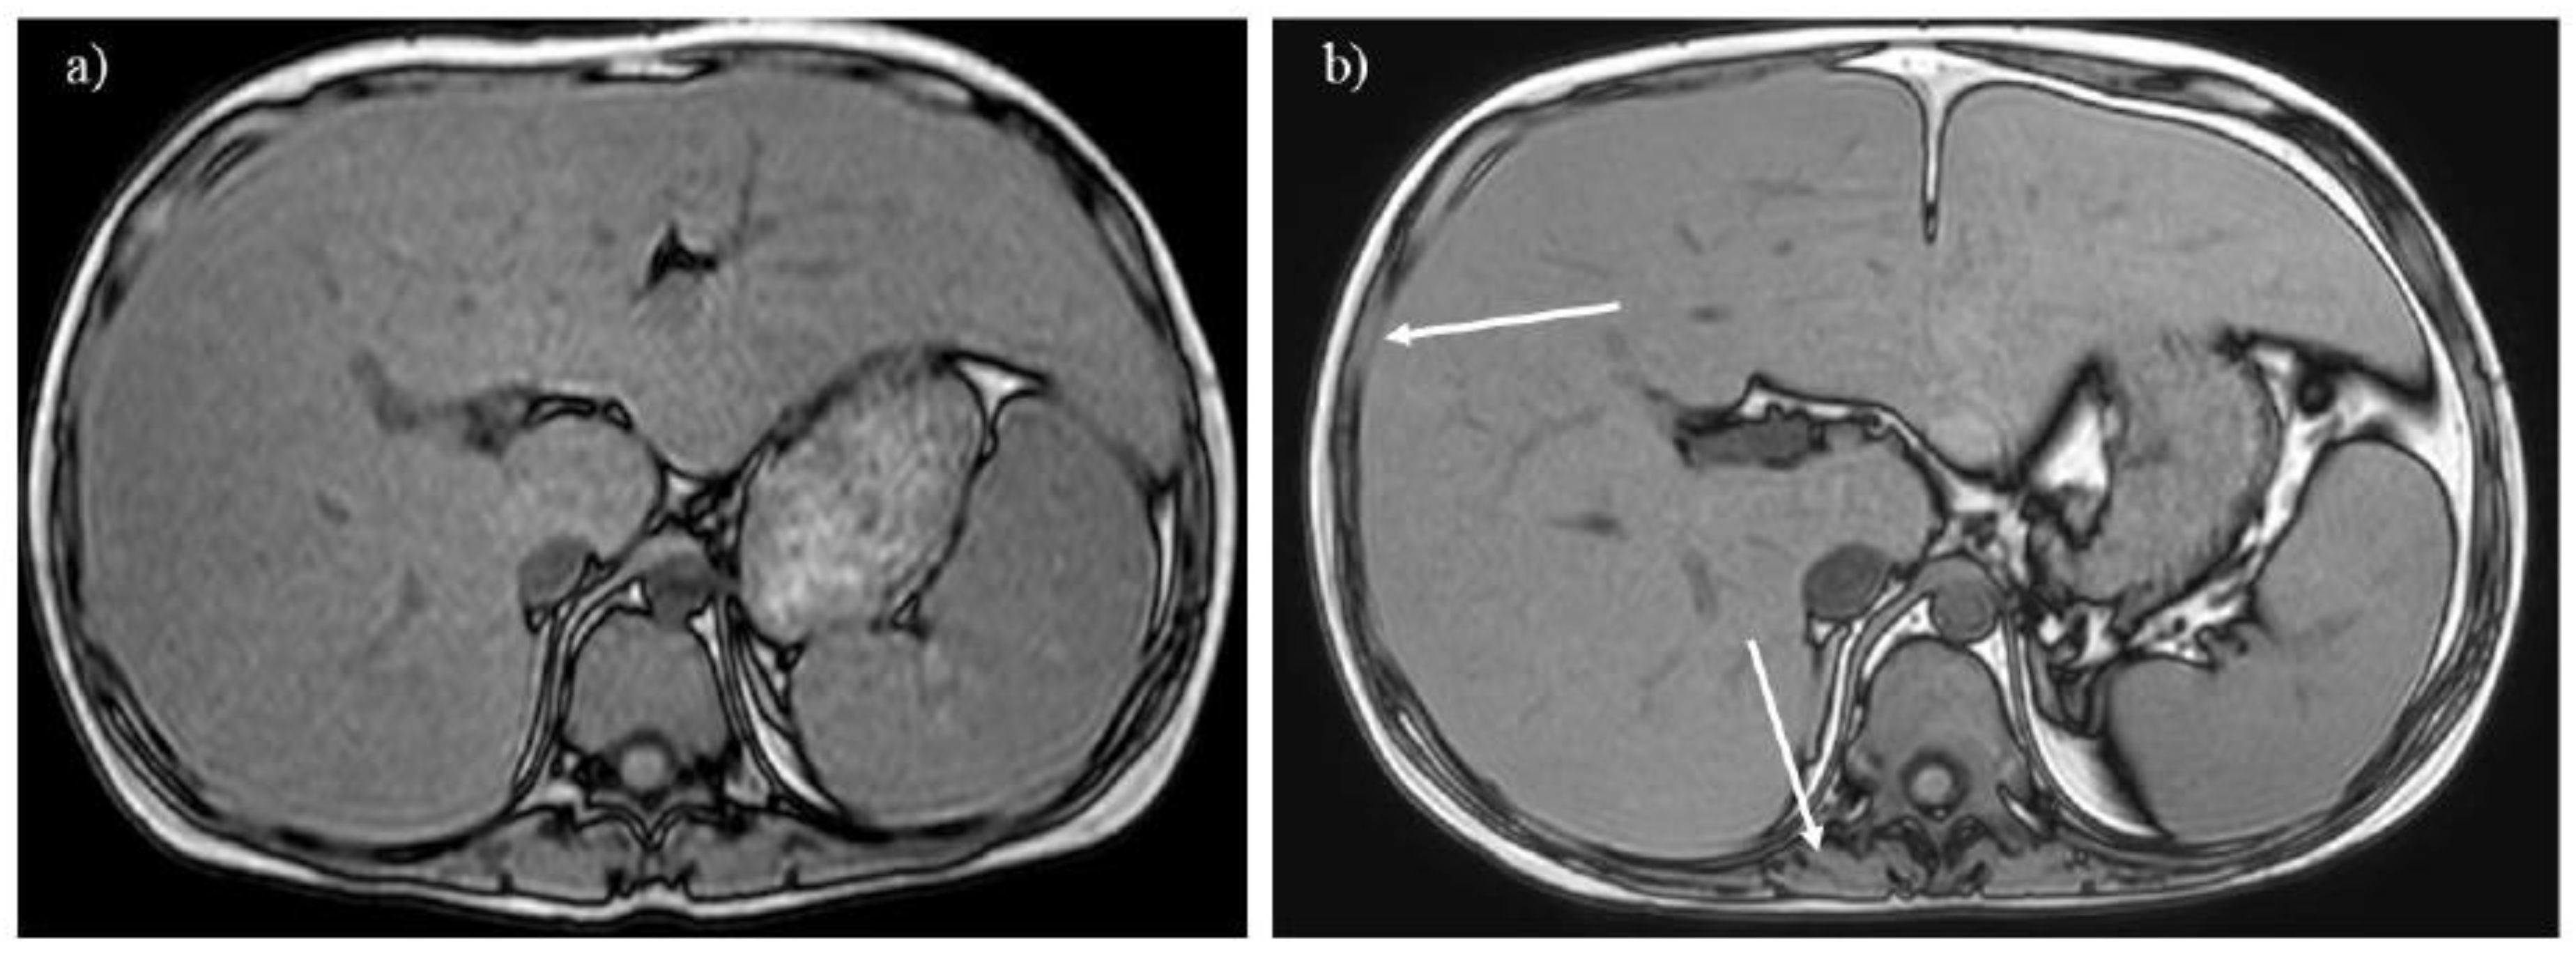

Figure 3. A 20-year-old woman with glycogen storage disease type Ia exhibiting enlargement of the kidney (A). Dynamic MRI (B) reveals a hepatic adenoma presenting strong enhancement in the arterial phase (arrow), and the tumor gradually enlarged over 13 years (C, arrow).

Hepatic adenoma and adenomatosis are common complications of GSDs [1,2,3,6,7,8]. Some genetic alternation may contribute to a larger hepatic adenoma in patients with GSD type Ia [3]. Different from hepatic adenomas without GSDs, those associated with GSDs are often found in male patients and multiple lesions (i.e., hepatic adenomatosis) and increase in size (Figures 3B, C, 7B and C) [17,18]. The hepatic adenoma associated with GSDs are not related to contraceptives. It is clinically problematic to differentiate between a growing hepatic adenoma and hepatocellular carcinoma. Indeed, hepatic adenoma can transform into hepatocellular carcinoma in the older patients with GSDs, exhibiting similar imaging appearances in GSDs (Figures 3C, 7B and 8) [9,17]. Multimodality imaging surveillance should be performed once a hepatic tumor presenting strong enhancement in the arterial phase is identified in patients with GSDs [6,9].

Glycogen and similar materials accumulate in the kidneys, which induces renal complications in patients with GSDs [1,2,3,5,14]. MRI is insensitive to renal calculi associated with GSDs, whereas it can detect enlargement or atrophy of the kidneys (Figures 2A and 3A). T1-weighted imaging identifies renal impairment as decreased corticomedullary contrast in the kidneys (Figure 2A) [15]. MRI can also be used to investigate transplanted kidneys without contrast agents (Figure 2B).